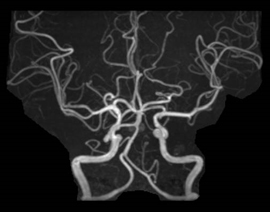

MRIはCTやX線撮影では分からない脳梗塞や、動脈瘤を可視化することができるため、脳卒中患者様においては重要な検査となっています。さらに、神経、靭帯、前立腺胆管、膵管などもよく分かるため、さまざまな診療科で需要は非常に高いです。